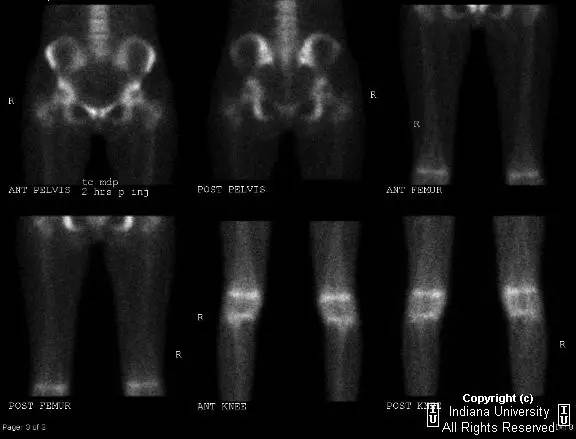

- 骨扫描:所有骨骼弥漫性摄取减少,表明骨质疏松。骨骺正常的摄取增加。无异常放射性摄取区域。

- 骨梗死骨扫描示由于血供障碍放射性示踪剂积累出现冷结节。